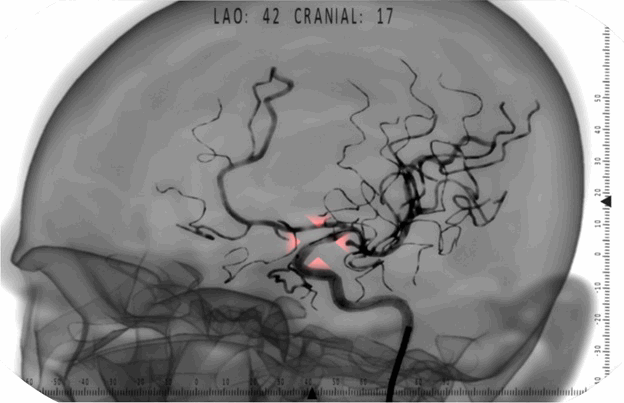

Я работаю в компании "Эйдос-Медицина", которая специализируется в разработке виртуальных медицинских симуляторов. Это специальные программно-аппаратные комплексы, позволяющие имитировать выполнение различных хирургических вмешательств в учебном процессе. Использование симуляторов позволяет студентам-медикам и интернам получить первые практические навыки по специальности до того, как им доверят живого пациента. Наша проектная группа разрабатывает симулятор рентгенэндоваскулярных вмешательств. Эта сфера включает в себя достаточно много видов операций на кровеносные сосуды, проводимых под контролем рентгеноскопии: ангиопластика, стентирование, спиральная эмболизация аневризм, эндопротезирование аневризм аорты.

Наша команда работает над проектом в своем текущем составе в течении полутора лет. Все идет своим чередом. Хирурги-консультанты прорабатывают с аналитиком тактику хирургических вмешательств шаг за шагом, работают с требованиями к визуальной составляющей. 3D-художник, используя КТ-ангиографию, анатомические атласы и советы хирургов, создает модели для новых клинических случаев симулятора. Программисты верхнего уровня трудятся над визуализацией рентгеноскопии, физикой движения эндоваскулярных инструментов внутри артерий, логическим анализом действий курсанта на симуляторе для фиксации правильности выполнения этапов вмешательства. Схемотехники, программисты микроконтроллеров и инженеры-конструкторы обеспечивают работу различных имитаторов медицинского оборудования, используемых в симуляции, сбор данных с датчиков, предварительную их обработку и отправку в программу. В ответ, на верхнем уровне подготавливается для передачи в контроллер информация, на основании которой обеспечивается соответствующая ходу виртуального вмешательства индикация на аппаратуре и эффекты обратной тактильной связи, призванные минимизировать условность учебного процесса.

Порядка 20 подобных сообщений в Solution. Что интересно, в этой библиотеке очень большие требования к производительности. В функциях, работающих с векторами и матрицами, в свое время считали буквально каждое умножение и искали, где можно сэкономить. Цикл в данном примере кода проходит очень большое количество итераций: до десятков тысяч. Он входит в алгоритмы системы частиц, которая обеспечивает рендер ангиографии. Особенность визуализации рентгеноконтрастого вещества в картине рентгеноскопии заключается в том, что сосуды направленные перпендикулярно плоскости кадра, выглядят темнее. Рентгеновское излучение проходит в этом случае вдоль сосуда, то есть проходит сквозь больший слой поглощающей среды, больше ослабляется и меньше засвечивает пленку в проекции. Этот эффект в программе достигается за счет системы полупрозрачных частиц, распределяющихся внутри полигональной сетки артерий. Полигональные сетки очень детализированные. Частиц в системе, соответственно, тоже очень большое количество. Интересно будет провести эксперимент. Сможем ли мы выиграть миллисекунду-другую, исправив эти неэлегантные места в коде? Возможно, компилятор делает эту оптимизацию автоматически, но почему не попробовать дать ему подсказку.